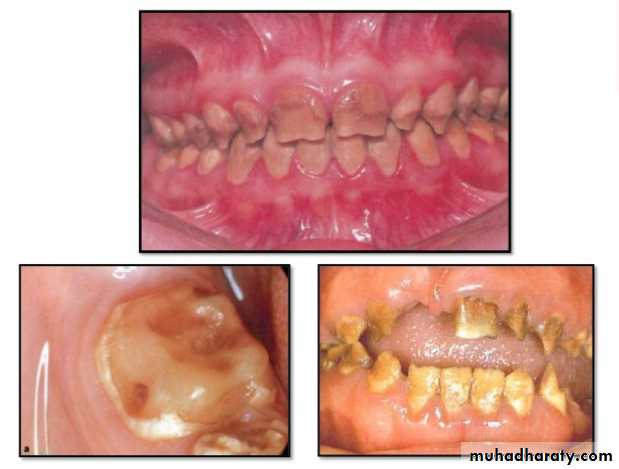

Amelogenesis Imperfecta

*It is a developmental disturbance that interferes with normal enamel formation.*It leads to marked changes in the enamel of all or nearly all the teeth in both dentitions.

*Most forms are autosomal dominant or recessive.

*Affects both dentition.

Enamel is composed mostly of mineral that is formed and regulated by the proteins in it. Amelogenesis Imperfecta is due to the malfunction of the proteins in the enamel.

* Classified based on pattern of inheritance:

hypoplasia.

hypomaturation.

hypocalcified.

* No treatment except for improvement of cosmetic

appearance.

Hypoplastic Amelogenesis Imperfecta:

* Due to some defect in ameloblasts enamel fails to develop to its normal thickness dentin exposed the tooth shows yellowish-brown color.*Enamel is randomly:

pitted .

rough OR smooth &glossy.

*The occlusal surfaces of the posterior teeth are relatively

flat with low cusps due to attrition of cusp tips that were initially low and not fully formed. An anterior open bite may be noted..

Generalized hypoplastic type

Amelogenesis ImperfectaAffects primary &permenant dentition

Severe mottling of the enamel surface.

Hypomaturation Amelogenesis Imperfecta:

*Enamel is normal in form on eruption but:

opaque.

white to brownish-yellow.

softer than normal.

tends to chip from underlying dentin.

Radiographically:

Affected enamel exhibits radiodensity similar to dentin.

Hypocalcified Amelogenesis Imperfecta:

*Enamel matrix is formed in normal quantity,poorly calcified.

When newly erupted:Enamel is normal in thickness, normal form, but weak , and opaque or chalky in appearance.

With years of function:

Coronal enamel is removed except for cervical portion that is occasionally calcified better.

Density of enamel & dentin are similar.